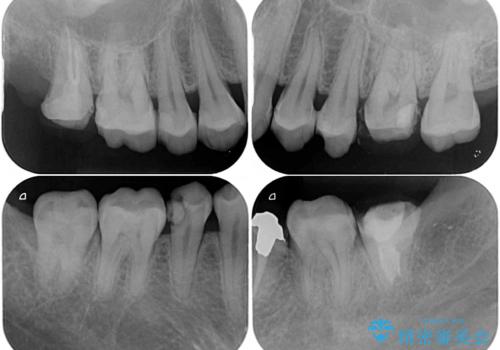

- 虫歯が多く、セラミッククラウンにより虫歯治療を行っている途中で矯正治療をしたいとのことで来院された患者様です。

上顎前歯が舌側に転位しており、なるべく早く楽に矯正したいとのことで、ワイヤー矯正を行うこととしました。

虫歯治療途中の歯は仮歯が装着されていたため、そのまま矯正治療を行い、矯正後に補綴治療を行うこととしました。